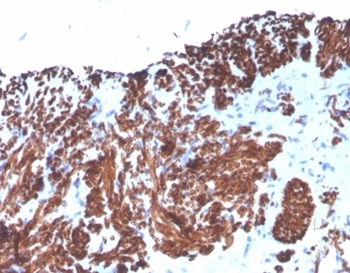

Formalin-fixed, paraffin-embedded human uterus stained with Desmin Mouse Monoclonal Antibody (DES/4526). HIER: Tris/EDTA, pH9.0, 45min. 2°C: HRP-polymer, 30min. DAB, 5min.

Cytoskeletal intermediate filaments (IFs) constitute a diverse group of proteins that are expressed in a highly tissue-specific manner. IFs are constructed from two-chain 伪-helical coiled-coil molecules arranged on an imperfect helical lattice, and have been widely used as markers for distinguishing individual cell types within a tissue and identifying the origins of metastatic tumors. Vimentin is an IF general marker of cells originating in the mesenchyme. Vimentin and Desmin, a related class III IF, are both expressed during skeletal muscle development. Desmin, a 469 amino acid protein found near the Z line in sarcomeres, is expressed more frequently in adult differentiated state tissues. Anti-desmin detects cells of normal smooth, skeletal, and cardiac muscles.Antibody reacts with leiomyomas, leiomyosarcoma, rhabdomyomas, rhabdomyosarcoma, and perivascular cells of glomus tumors of the skin.